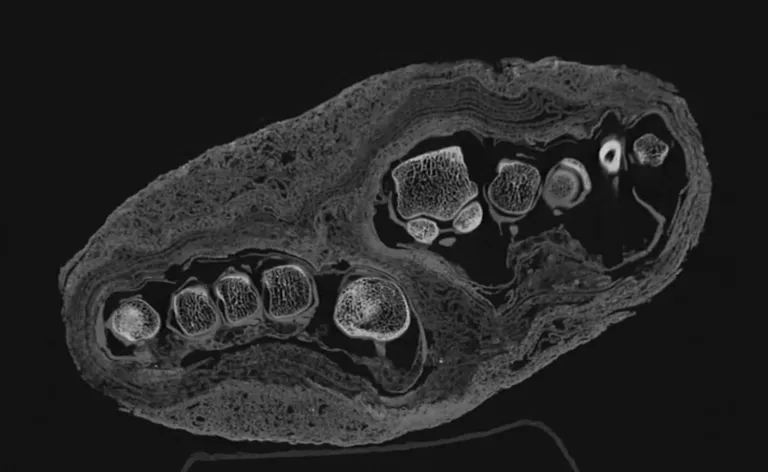

木乃伊牙齿CT扫描。图片来源:uux.cn医学影像中心 / 森梅尔韦斯大学

从顶部做木乃伊脚部CT扫描。图片来源:uux.cn医学影像中心 / 森梅尔韦斯大学